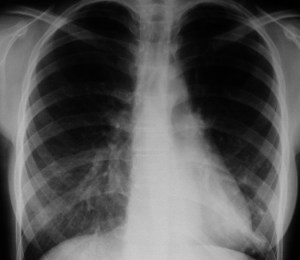

SIGNO DEL ARCO AÓRTICO OCULTO

En la radiografía lateral de tórax, se ha descrito que la ausencia de la imagen del arco aórtico puede ser la clave diagnóstica de coartación aórtica. La imagen izquierda muestra el signo. Se trata del mismo paciente del Signo de las muescas costales (ver Otros signos de pleura/pared). La imagen derecha corresponde a una radiografía normal con la sombra aórtica visible (flecha).

Se han propuesto varias explicaciones para este signo; puede ser debido a hipoplasia del arco aórtico combinada con la coartación, a dilatación de las arterias braquiocefálicas (particularmente la arteria subclavia izquierda) que oscurecen el margen superior del cayado, o a hipoplasia y desplazamiento anteromedial de la porción distal del arco aórtico.

Este artículo de Chen es la referencia: Obscured aortic arch on the lateral view as a sign of coarctation. Radiology 1984: 153; 595-596.